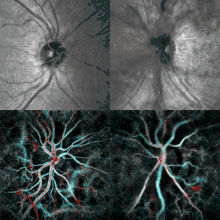

Checking the eyes for signs of papilledema should be carried out whenever there is a clinical suspicion of raised intracranial pressure, and is recommended in newly onset headaches. This may be done by ophthalmoscopy or fundus photography, and possibly slit lamp examination.